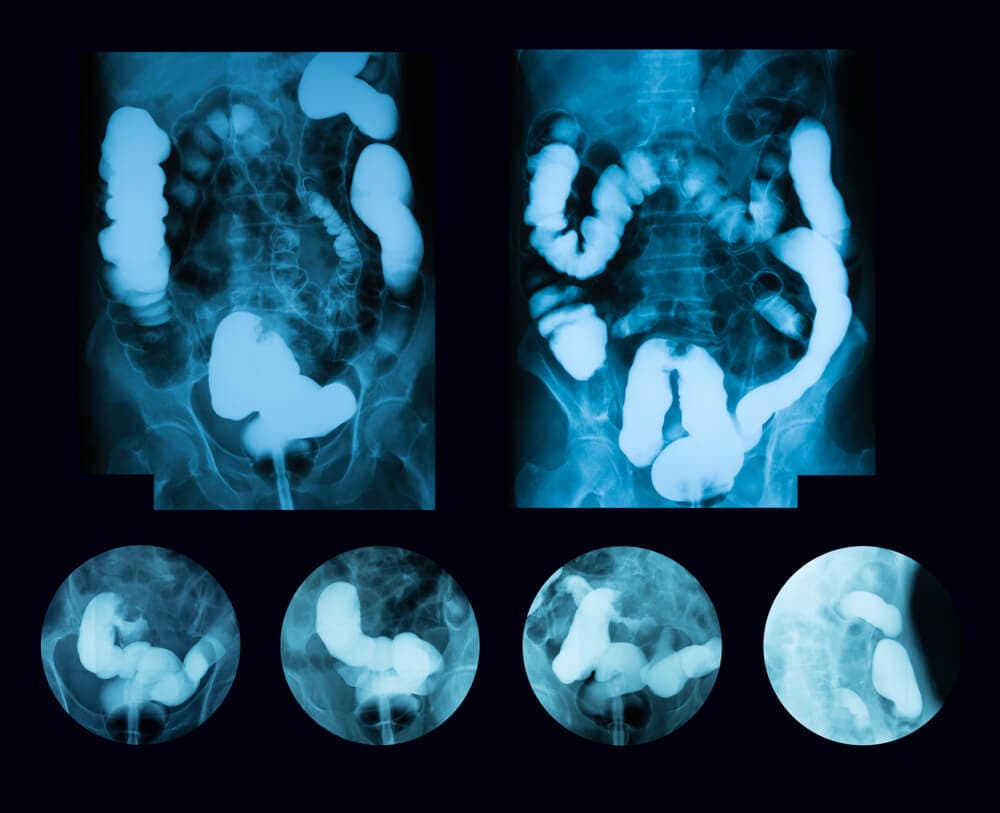

También auscultará la zona abdominal con el estetoscopio para escuchar los ruidos intestinales. Lo más probable es que ordene algunos exámenes para corroborar el diagnóstico, como los siguientes:

- Radiografía abdominal.

- Tomografía computarizada del abdomen.

Para diagnosticar el megacolon tóxico el médico tomará en cuenta los síntomas e indagará sobre los antecedentes de enfermedad inflamatoria intestinal. Luego, hará una exploración física en la que palpará el abdomen para verificar si hay dolor.